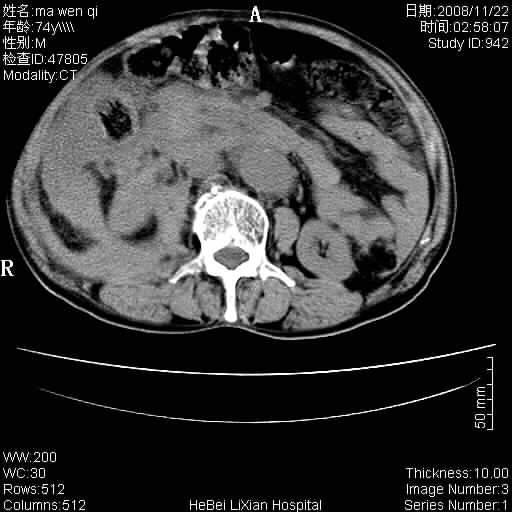

患者男 74岁.突然昏迷,休克6小时.血压70/30,头颅ct未见异常,既往体健.

补充病史,保留导尿10小时,尿袋内只有少许尿液,患者于住院后15小时后去世.

腹主动脉、双侧髂动脉夹层动脉瘤破裂出血进入腹腔。

1)考虑双侧髂动脉瘤并右侧动脉瘤破裂出血,右侧腹膜后及腹腔积血。2)双侧腹股沟疝。

1)考虑,腹主动脉、双侧髂动脉夹层动脉瘤破裂伴右侧腹膜后及腹腔积血。2)双侧腹股沟疝。

1)考虑胸、腹主动脉、双侧髂动脉瘤并右侧动脉瘤破裂出血,右侧腹膜后及腹腔积血。2)双侧腹股沟疝。